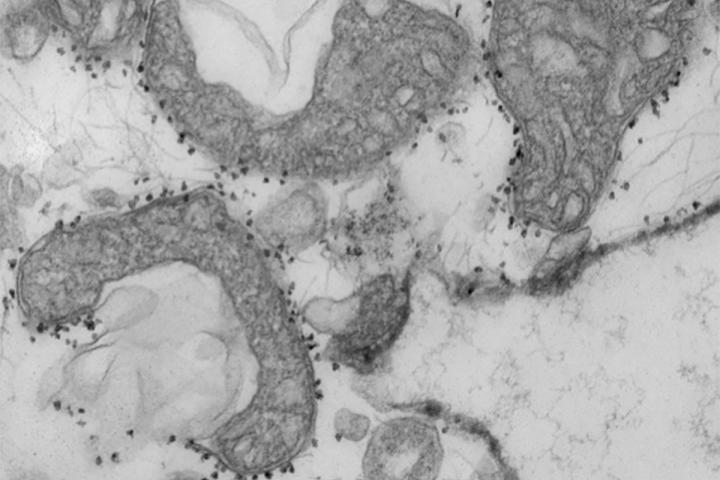

image: A new study from Washington University School of Medicine in St. Louis suggests that measuring mitochondrial DNA in the blood of patients with COVID-19 can help predict which patients are at highest risk of severe disease, requiring more intensive care. Mitochondrial DNA levels are a measure of tissue damage. Pictured are damaged mitochondria (dark grey areas) released from human lungs. The small dark dots surrounding the mitochondria are magnetic beads that carry antibodies used to isolate and study unhealthy mitochondria that have been released from dying tissues.

The blood test measures levels of mitochondrial DNA, a unique type of DNA molecule that normally resides inside the energy factories of cells. Mitochondrial DNA spilling out of cells and into the bloodstream is a sign that a particular type of violent cell death is taking place in the body.

"Viruses can cause a type of tissue damage called necrosis that is a violent, inflammatory response to the infection," Gelman said. "The cell breaks open, releasing the contents, including mitochondrial DNA, which itself drives inflammation. In COVID-19 patients, there has been anecdotal evidence of this type of cell and tissue damage in the lung, heart and kidney. We think it's possible that measures of mitochondrial DNA in the blood may be an early sign of this type of cell death in vital organs."